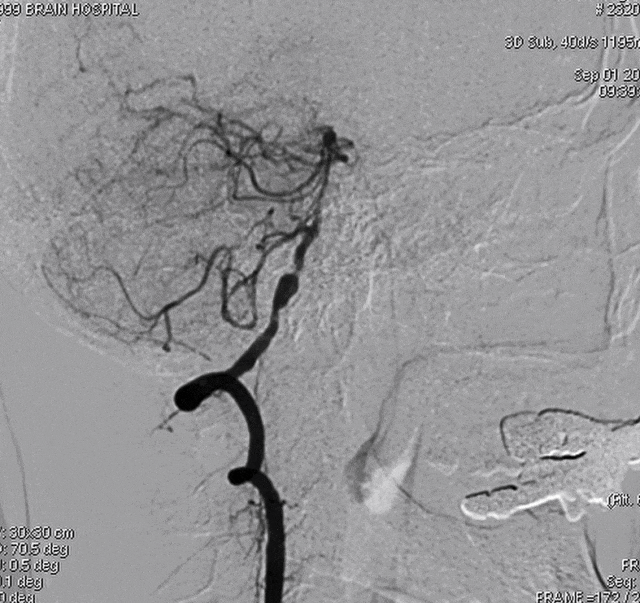

DSA示双侧椎动脉V4段狭窄,右侧为著且合并梭形动脉瘤。

术前DSA。